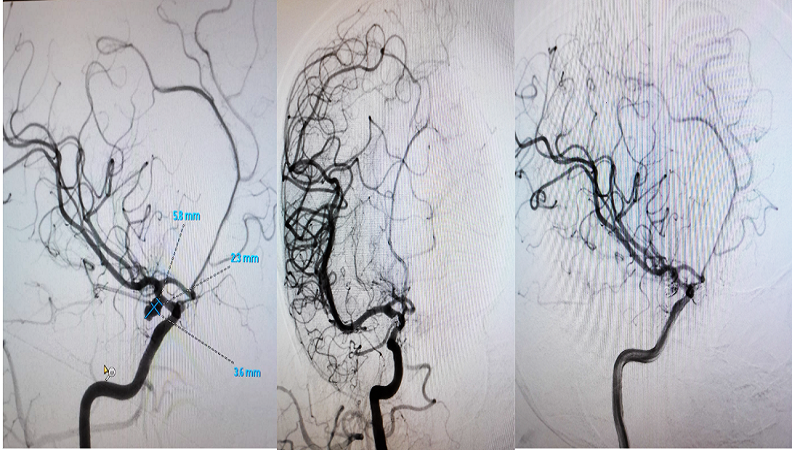

Brain Aneurysm Coiling

Brain aneurysm coiling is a minimally invasive procedure that uses tiny coils to block blood flow into an aneurysm, preventing rupture and stroke